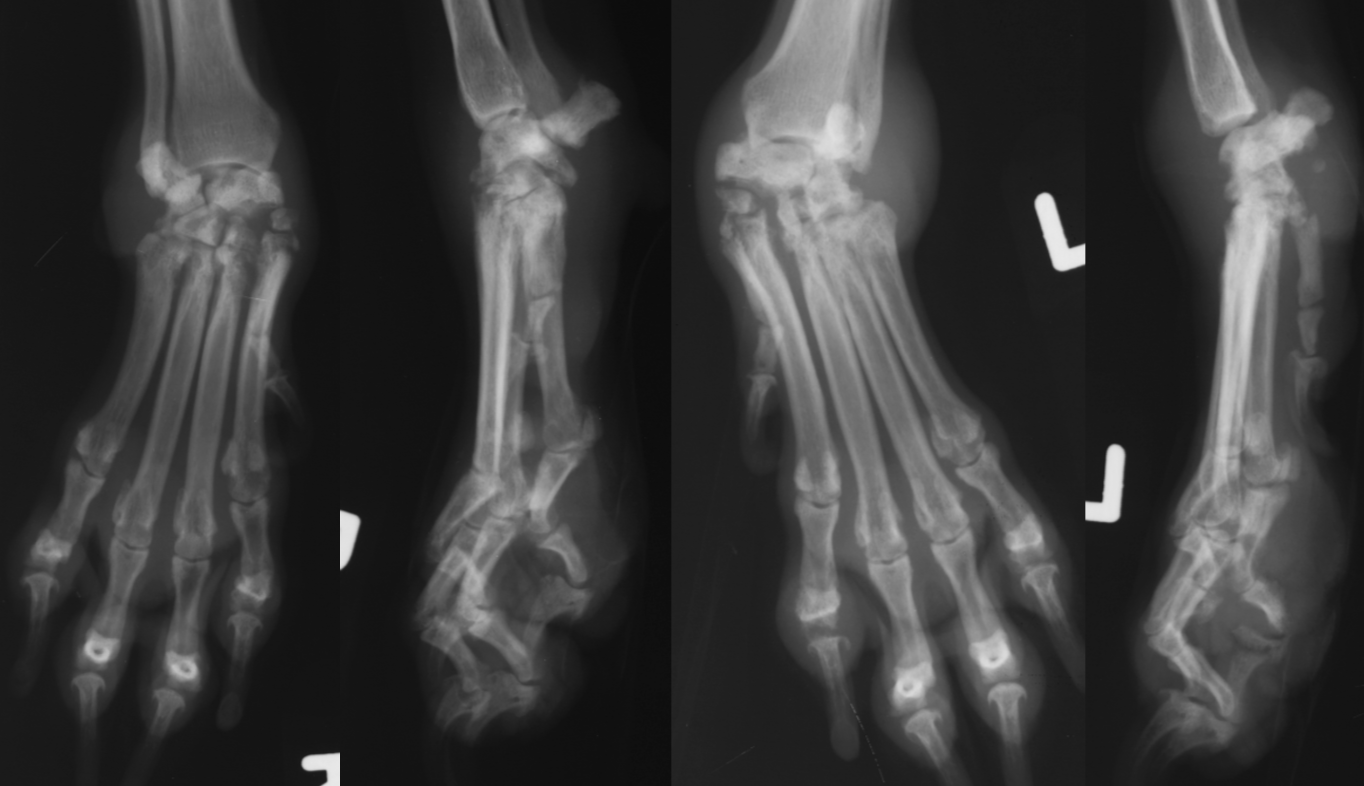

hypertrophic osteopathy signalment

middle to older dog

secondary to thoracic or abdominal dz/mass

spares small bones of carpus and tarsus

starts from MC/MT bones and goes up the leg symmetrically and bilateral

NO lysis but LOTs of periosteal rxn

AGG lesion

Hypertrophic Osteopathy